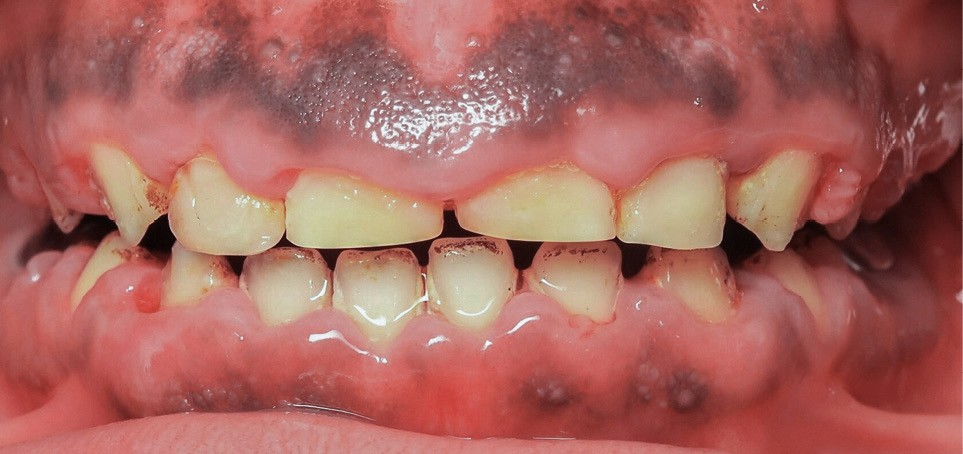

L’examen exobuccal met en évidence un profil dolichofacial et des anomalies majeures de structure dentaire (fig. 1). L’examen intrabuccal (fig. 2) montre :

- une hypoplasie sévère de l’émail ;

- une hyperplasie gingivale inflammatoire ;

- des hauteurs coronaires très réduites ;

- des couronnes pédodontiques sur les premières molaires permanentes ;

- des caries sur 17 et 27 ;

- des défauts d’éruption des quatre deuxièmes molaires permanentes ;

- de nombreux diastèmes et l’absence des dents de sagesse.